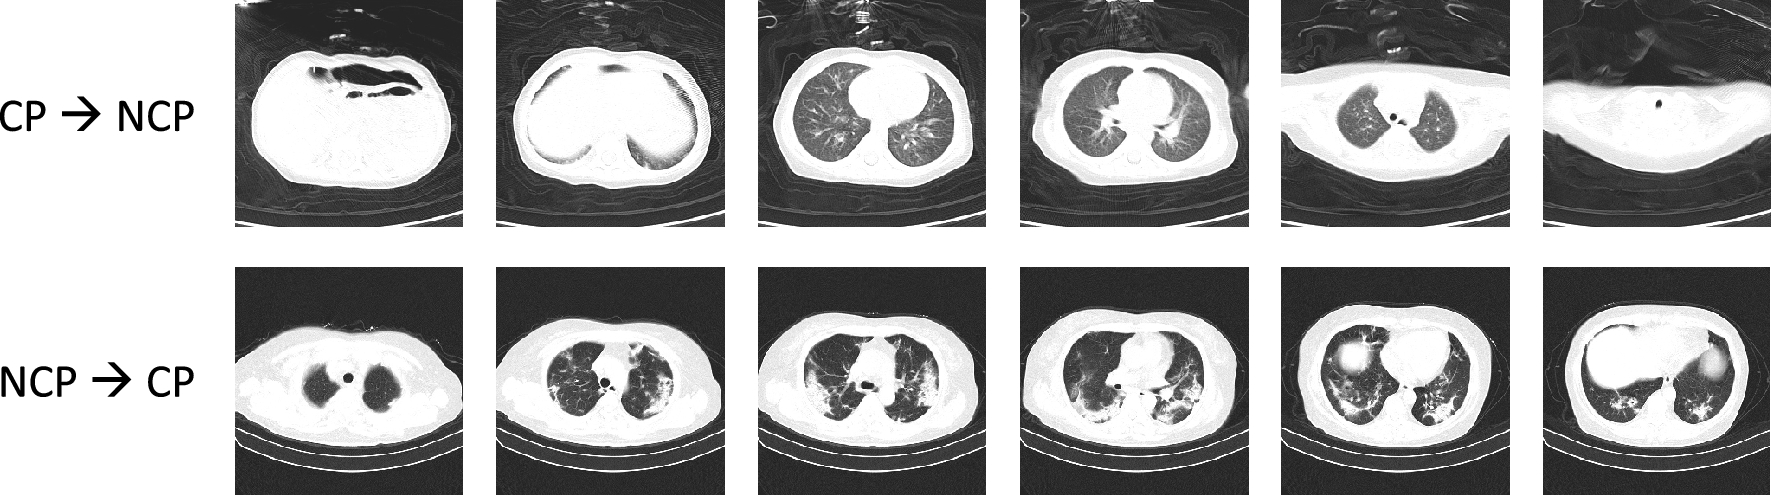

Figure 6

Two failure cases of our method. Each row contains some slices of a target CT scan. The first CT scan is from the CP class, but is incorrectly predicted as being from the NCP class. The second CT scan is from the NCP class, but is incorrectly predicted as being from the CP class. The cause of failure is that the two types of pneumonia have similar findings in CTs, which makes it challenging to distinguish them.